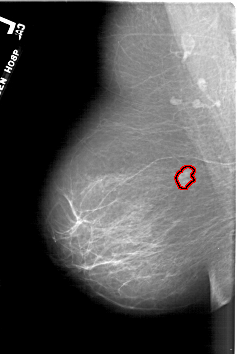

FILE: A_1865_1.LEFT_MLO.OVERLAY

TOTAL_ABNORMALITIES 1

ABNORMALITY 1

LESION_TYPE MASS SHAPE LOBULATED MARGINS OBSCURED

ASSESSMENT 4

SUBTLETY 4

PATHOLOGY BENIGN

TOTAL_OUTLINES 1

BOUNDARY